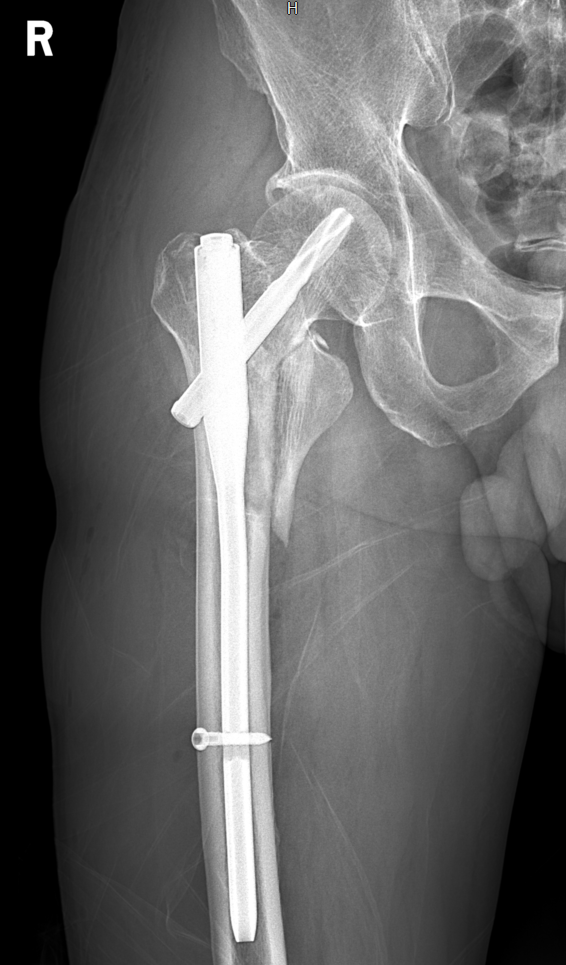

排除手术禁忌症后,于我院在“椎管内麻醉”下行“右侧股骨转子间骨折闭合复位髓内钉内固定术”,术后安返病房,行抗炎、消肿、止痛等积极对症治疗。

术后影像学检查: